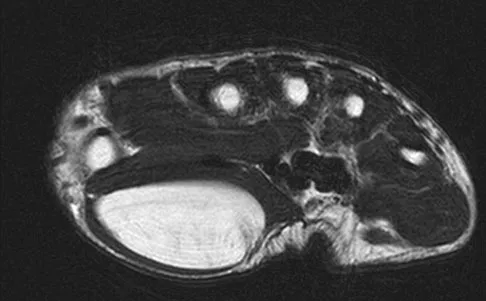

Figures 35a and 35b show the axial T2-weighted and coronal T1-weighted MRI scans of a patient who has enlargement of the right thigh. What is the most likely diagnosis?